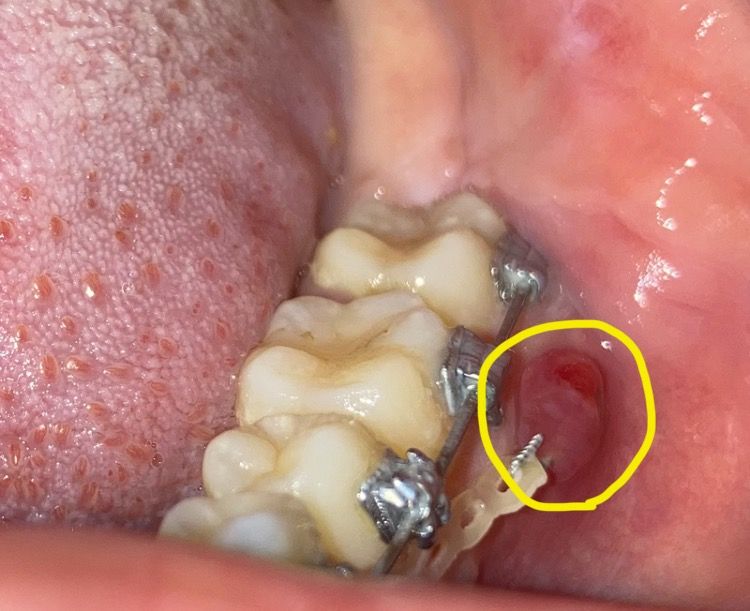

이거 지금 잇몸 염증 심각한 것인가요?

미니스크류를 기존의 자리에서 뒤로 이동시켜 식립했는데요.

5월 7일에 이동해서 식립했고 그 사이에 왼쪽만 염증이 생겨서 턱 통증이 있고 고름이 나오길래 5월 12일에 치과에 가서 염증치료하고 약처방 받았습니다.

5일치 약 먹을만큼 염증이 쉽사리 잡히지 않았는데요. 결국 약 끊은지 5일만에 다시 염증이 생겼는지 뭐가 볼록 튀어나와 미니스크류를 뒤덥더라구요. 그런데 이전처럼 통증이 느껴진다거나 고름이 보이진 않았습니다.

결국 이게 커서 미니스크류는 보이지 않고 사진처럼 되었습니다. 많이 심각한가요?

(사진은 양치 중에 찍은거라 교정기 주변이 더러워 보입니다. 이 점 참고해서 봐주시면 감사하겠습니다.)

사진으로 봤을 경우에는 잇몸이 자극이 되어 증식된 것으로 보입니다. 염증의 원인이 스크류 때문이라면 스크류를 제거해야 할 수 있지만 단순히 조직의 과민으로 인해서 자라나온 부분이라면 단순하게 다듬을 수도 있습니다.

미니스크류가 잇몸 염증을 유발하는 원인인 것 같습니다. 약처방으로도 개선안된다면 일단 미니스크류를 제거해보고 증상 또 지켜봐야 할 겁니다.